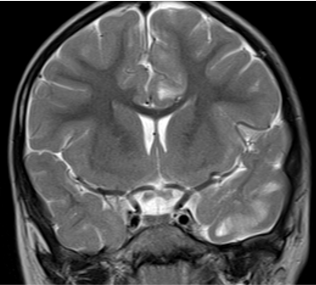

• Coronal CT Chest lung window showing peripheral ground glass opacity (black arrow).